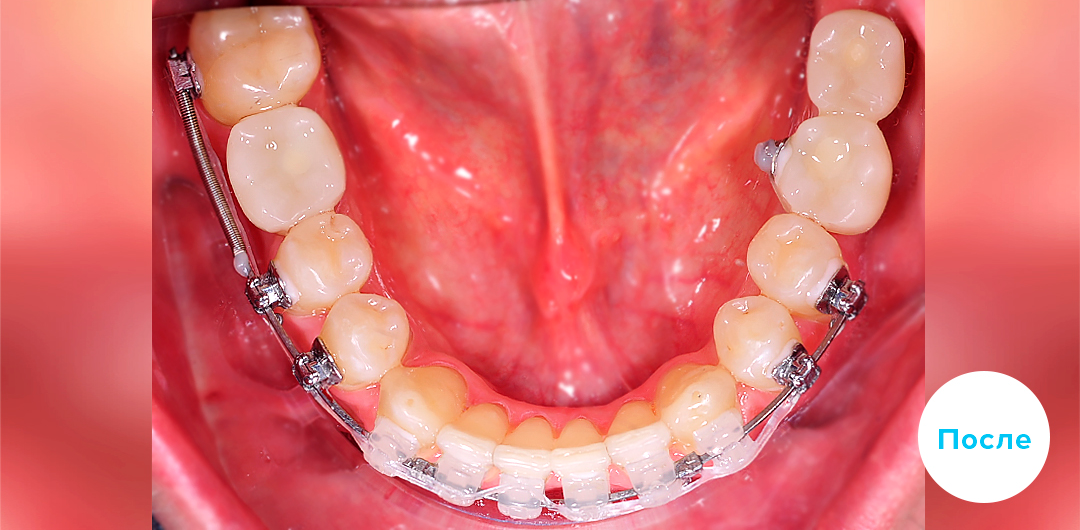

До

После

ЛЕЧЕНИЕ ДЕФИЦИТА МЕСТА НА ЧАСТИЧНОЙ БРЕКЕТ-СИСТЕМЕ У ДЕТЕЙ

Смотреть кейс